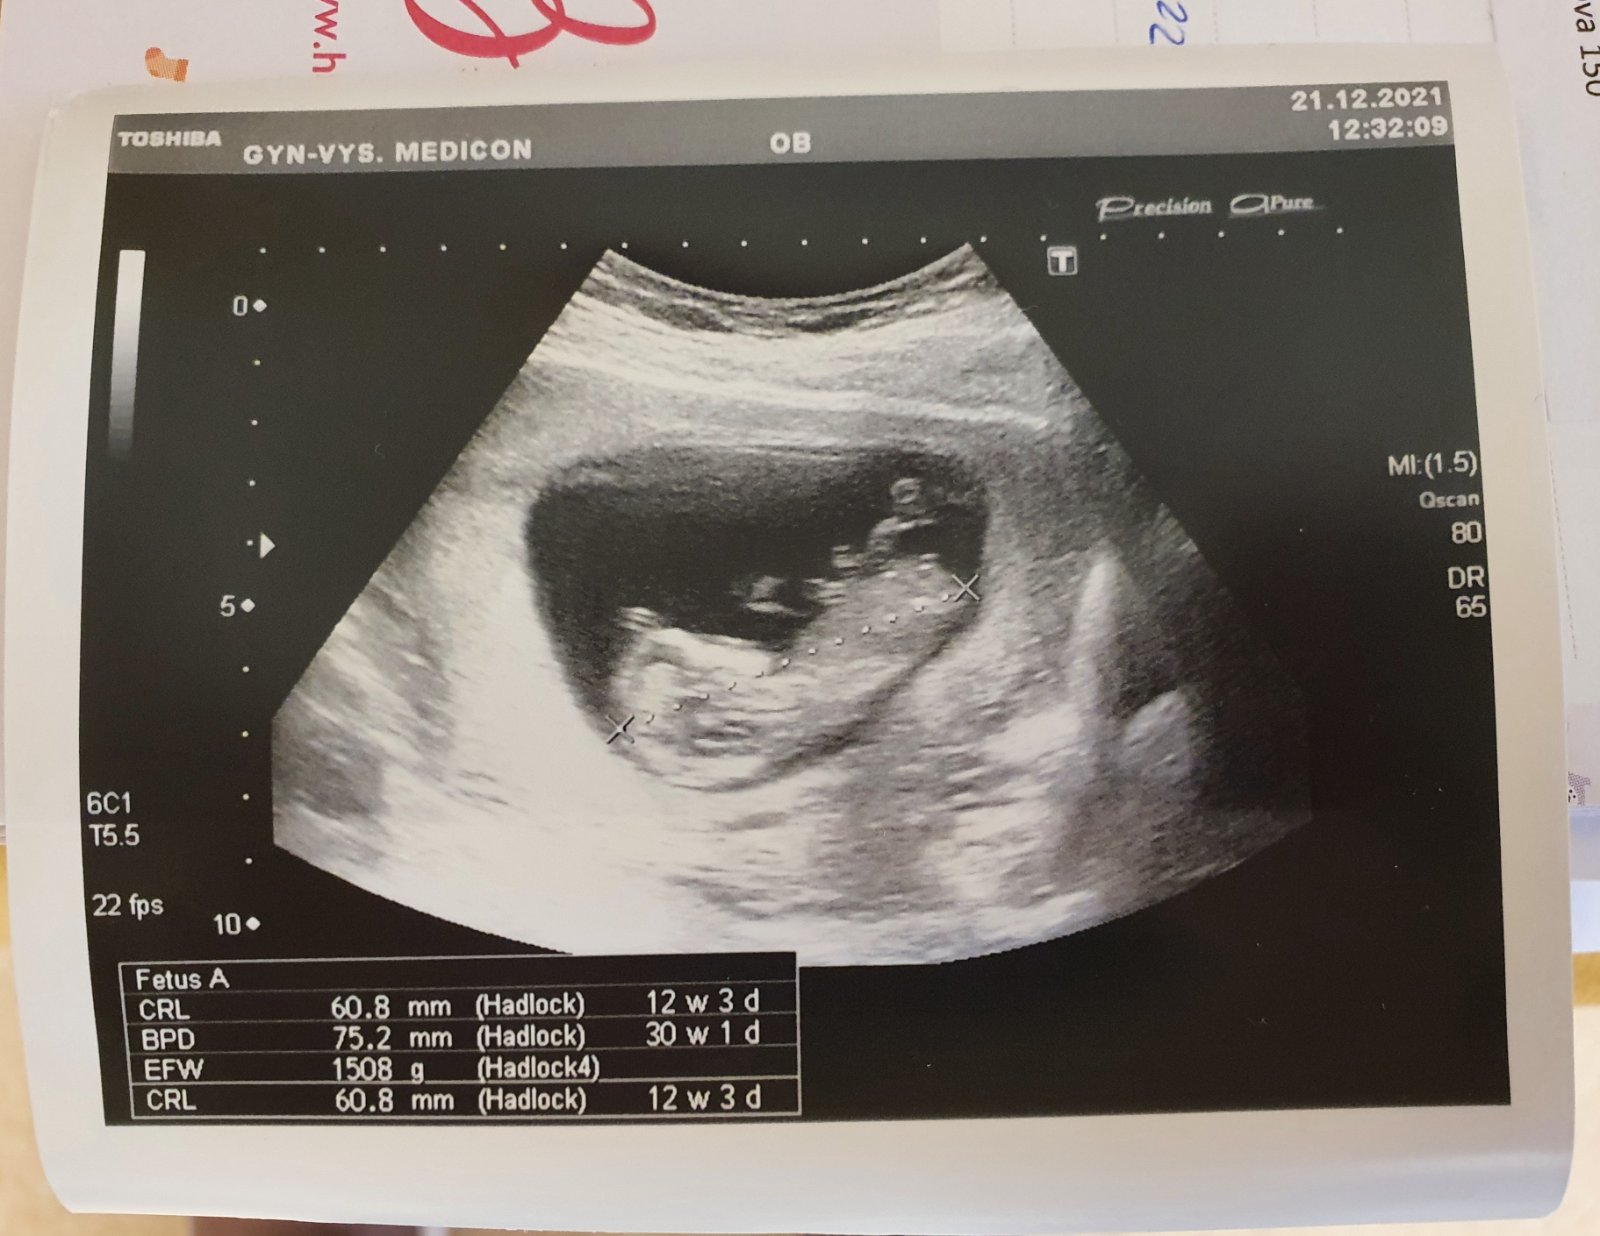

Jak poznat pohlaví? Diskutujeme možnosti.

21. pro 2021

Zovna z tehle fotky to asi vidět není, ale jinak se pohlaví určuje právě z profilu a už od 6 cm to jde dobře u většiny určit.

Z tohohle to fakt nepůjde poznat. Mě vždycky doktor dal fotku, na které byl zadeček a pohlaví zespodu, jako kdyby pohled ze záchodové mísy.